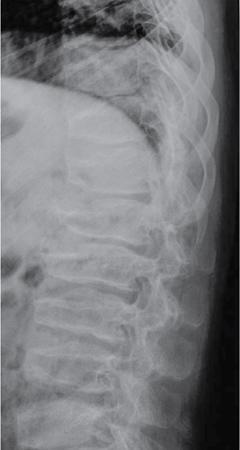

MISCELLANEOUS PAEDIATRIC RADIOGRAPHY – TECHNIQUES AND INTERPRETATION: SKELETAL SURVEY Padma V. Badhe The skeletal survey, generally performed in children, is a set of radiographs done in order to evaluate the entire skeleton. A skeletal survey, commonly used to evaluate skeletal dysplasias, acquired metabolic disorders and suspected child abuse, is still the key radiological investigation for the same. Hence, an explicit understanding of the technique along with the common disorders forms the basis of making a diagnosis in these paediatric pathologies. A skeletal survey is done for various skeletal dysplasias, non-accidental injury (battered baby syndrome) and suspected child abuse. It can also be done in cases of metabolic bone diseases, disseminated infections, multiple myeloma, eosinophilic granuloma. It is also used in evaluation of metastatic bone diseases and polyarticular arthropathy. Orthogonal views of the skull, spine, pelvis and one extremity are taken, preferable in standing position. For preterm babies/newborns, AP and lateral views of babygram may be taken. Projections: For skeletal dysplasias: Additional views: Both extremities may be taken if epiphyseal abnormalities and limb asymmetry is present. Focused views for specific pathologies may be taken. When a diagnosis remains uncertain, 1 year follow up is usually recommended. For preterm babies/newborns: AP and lateral views of babygram may be taken with additional specific views for extremities. For suspected non-accidental injury (NAI): AP and oblique view of chest is taken for better evaluation of the ribs. AP view of abdomen with pelvis. Both upper and lower limbs are evaluated. In lower limbs, two projections in AP and lateral (one with both femur including hip and knee joints; and another for foot and ankle) is taken. AP and lateral views of whole spine, skull. Oblique view of hands. A babygram should be avoided in cases of NAI, as subtle fractures are easily missed. Proper legal documentation while taking the views is very important and ideally two health care professionals must be present. For metabolic disorders: entire skeletal survey is usually not required. Specific views of hands, knees and spine may be taken with additional views depending on the suspected pathology. Centring point: Varies according to the part being examined. Angulation, collimation and orientation: Varies according to the part being examined. Images must be well collimated to obtain lower radiation dose. Detector size: Varies according to the part being examined: 8″ × 10″, 10″ × 12″, 11″ × 14″. Exposure: Ideally high kVp images are taken to reduce radiation dose. But in suspected NAI, low kVp/high mA images are recommended to better demonstrate findings. SID (Source Image Distance):100 cm Grid: Grids are not routinely used to image spine, pelvis, skull and abdomen in children. Radiation dosage: 0.3–3 mSv Essential image characteristics: Adequate spatial resolution, high signal to noise ratio, low kVp (50–70) for high contrast should be done. Excellent bone and soft tissue details are required. The presentation of skeletal dysplasia can range anywhere from minimal stunting of growth and bowing of limbs to severe dwarfism and multiple fractures. Knowledge of the commonly encountered dysplasias with an approach to arrive at a diagnosis is vital in any Radiologist’s practice The following flow chart summarizes the classification of important skeletal dysplasia: The following table summarizes the various dysplasias affecting the axial skeleton: TABLE 7.5.1.1 The following flow chart summarizes the working approach to skeletal dysplasias: Osteopetrosis (Albers-Schonberg disease/Marble bone disease) (Fig 7.5.1.1): Osteopetrosis clinically presents with anaemia/thrombocytopenia or cranial nerve compression. Radiological features include generalized increase in bone density with loss of medullary space. However, cortico-medullary appreciation with cortical thinning is also rarely seen. Bone within bone appearance with Erlenmeyer flask deformity is also noted. Pyknodysostosis (Figs. 7.5.1.2 and 7.5.1.3): patient presents with short stature. Unlike osteopetrosis, there is no anaemia. Radiographs show generalized increase in bone density with preserved medullary canal. There is mandibular hypoplasia with obtuse angle. Acro-osteolysis is also a feature. Dental caries with osteomyelitis of the jaw may be seen. Sclerosing dysplasia presenting as wavy undulating new bone formation. Usually monomelic, lower limb and along one side. The classic appearance is described as Dripping candle Wax sign. It is a Sclerosing dysplasia with radiological features of symmetric juxta-articular involvement in epimetaphyseal region. They are 1–10 mm in diameter and uniform in size. No metabolic activity is seen on bone scans. This skeletal dysplasia shows diffuse decrease in bone density with paper-thin cortex. Fractures heal in normal time but shows callus with poorly cellular matrix. Wormian bones and enlarged sinuses may be seen. Codfish vertebra (Biconcave vertebra) may be seen. Metaphyseal corner fractures are not seen in osteogenesis imperfecta that helps to differentiate it from battered baby syndrome. There are four types of OI out of which type one is most common (Figs. 7.5.1.6 and 7.5.1.7). The radiological features of MPS include Osteopenia and Universal platyspondyly. The intervertebral disc spaces are maintained. Proximal pointed metacarpals is an important radiological finding. Hurler’s syndrome show anteroinferior beaking with short and wide metacarpals. Varus deformity of humerus is characteristically seen in Hurler’s syndrome (Fig. 7.5.1.8). Mental retardation & corneal clouding is seen in Hurler’s syndrome whereas these Hunter’s disease has normal intelligence with no corneal clouding. Morquio’s syndrome shows central beaking (Fig 7.5.1.9). This skeletal dysplasia shows normal bone density with rhizomelic limb shortening and normal trunk. Narrowing of spinal canal is classically seen with decrease in the Interpedicular distance caudally. Other radiological features include trident hand (separation of middle & third fingers), Champagne glass pelvis (short, flat ilia and small sciatic notch), bullet nose vertebra and overexpansion of skull with narrow foramen magnum (Fig. 7.5.1.10). This skeletal dysplasia is characterized by normal bone density with dwarfism and normal craniofacial skeleton. The interpedicular distance is normal. There is severe platyspondyly with anterior tonguing (disappears at older age). Other radiological features include increased disc space, short stubby metacarpals, small irregular epiphysis and widened metaphysis. Anterior tonguing is a feature of Pseudoachondroplasia. This form of skeletal dysplasia involves the spine and epiphyses (Fig. 7.5.1.11). There is normal bone density with rhizomelia. Spine and Pelvis can be involved. Premature osteoarthritis can be seen. The other characteristic features include Platyspondyly and small irregular epiphysis. There are two forms Spondyloepiphyseal dysplasia Congenital and Spondyloepiphyseal dysplasia Tarda. Spondyloepiphyseal dysplasia Congenita is Autosomal dominant and shows pear-shaped vertebrae. Spondyloepiphyseal dysplasia Tarda is X Linked recessive with heaped up vertebrae. It has two forms. The first form is Conradi Hunermann syndrome which is autosomal dominant characterized by asymmetric limb shortening with metaphyseal flaring (Fig. 7.5.1.12). The Autosomal recessive form is Fatal in first few years. Rickets: Rickets refers to deficient mineralization of the growth plate in the paediatric population due to deficiency of vitamin D. In an immature skeleton, there is abnormal mineralization at the zone of provisional calcification in the metaphysis due to osteoid deposition resulting in widening of the growth plate. The features of rickets include fraying, splaying and cupping (Fig. 7.5.1.13). Fraying denotes indistinct margins of the metaphysis whereas splaying denotes widening of metaphyseal ends. Term ‘Cupping’ is used for increased concavity of the metaphysis. These findings are typically seen involving areas of active growth (e.g. distal femur and proximal tibia in the knee) Bowing is a result of associated osteomalacia leading to weakening of weight-bearing lower limb bones. Other bone deformities such as genu valga, genu varum, protrusio acetabuli can also be seen. The lower ribs may also be drawn inwards inferiorly by the attachment of the diaphragm this is called Harrison’s sulcus. Scurvy: Scurvy is a result of dietary deficiency of Vitamin C (ascorbic acid). The classic presentation is that of a patient with an increased bleeding tendency and osteopenia with poor wound healing. Features of scurvy include generalized osteopenia with cortical thinning termed as ‘pencil-point’ cortex. Other radiological findings include the periosteal reaction due to subperiosteal haemorrhage. Expansion of the costochondral junctions occurs forming scorbutic rosary. Bleeding into the joint spaces may result in hemarthrosis. Circular, opaque radiologic shadow surrounding epiphyseal centres of ossification may result from bleeding (Wimberger ring sign) (Fig. 7.5.1.14). Frankel line may be seen. It represents dense zone of provisional calcification. Lucent metaphyseal band is seen underlying Frankel line called as Trümmerfeld zone. Metaphyseal spurs may be seen that result in cupping of the metaphysis (Pelkin spur). Pelkin fracture (metaphyseal corner fracture) can also be seen. Images obtained must be of good resolution with adequate bone and soft tissue details. Additional views: They have already been described in positioning. CT Brain in can be done in cases of NAI to look for subdural hematomas. A skeletal survey is the first-line imaging modality for evaluation of skeletal dysplasia, nonaccidental injury and metabolic bone diseases. The skeletal survey must be tailored according to the respective indication. It helps to characterize syndromic patterns in skeletal dysplasias, with evaluation of complications. In cases of diagnostic dilemmas, additional focused view and occasionally yearly follow-up is recommended. A high index of suspicion is needed in utilizing skeletal survey as a diagnostic modality in NAI. At the same time, one must also remember the legal and social implications of making this diagnosis. BABYGRAM Babygram is a colloquial term used for a radiograph of the whole body of a newborn or just the chest and abdomen (thoracoabdominal babygram) on a single image. As the name suggests it is a rather non-targeted study. It is most commonly requested after line placement. Evaluation of skeletal abnormalities in a deceased foetus is typically performed using anteroposterior and lateral views of a babygram. It helps in pointing out skeletal causes of death in stillborn or dead foetuses. This will help the treating physician and parents understand the reason for baby’s death. This will also help in future genetic counselling of the couple. Sometimes chest or abdominal radiographs of the baby are requested but due to radiographers error or inexperience with small babies, there is inclusion of the region not to be assessed leading to a false babygram. Babygram is most frequently done after line placement in neonates, to view the position of the umbilical vein or artery catheter and to confirm appropriate placement. It is a useful modality in skeletal dysplasias (Fig. 7.5.1.15) like osteogenesis imperfecta, thanatophoric dysplasia and chondrodysplasia punctata. It can also be used for skeletal deformations probably caused by foetus akinesia and in cases of Caudal regression syndrome. In stillborn foetuses, it is used for evaluation of skeletal dysplasias prior to an autopsy (Fig. 7.5.1.16). It is also used in screening for surfactant deficiency and in cases of Necrotizing Enterocolitis in preterm babies where it can help to see the bowel dilatation, intramural and portal venous gas. It can be done in aneuploidies like trisomy 18 and in cases of sudden infantile death syndrome. All the essential equipment and room need to be prepared including the exposure factor. This should be done prior to placing the baby on the table to prevent any neonatal heat loss. Ensure that the baby is correctly identified. Give brief explanation to the patient’s parents regarding the procedure, its risks and benefits. Ensure that the accompanying relative is not pregnant (if female). Parents/guardians/nurses should be instructed to hold the baby with arms above the head and legs straight down. Sandbags/tapes can be used to immobilize the baby. Avoid taking the radiograph when baby is crying. Normal appearance: The endotracheal tube should lie in the lower third of trachea, distance can vary with position of baby’s head. Umbilical artery catheter has an inferior dip along the internal iliac artery, which then turns superiorly along the aorta. The tip should lie in the mid-thoracic aorta (T6–T10) or lower (L3–L4) away from aortic branches to prevent any thrombosis. Umbilical venous catheter does not have the inferior curvature, but rather a posterolateral angulation to the right near the liver through the ductus venosus. The tip should lie in the superior IVC or right atrium at T8/T9 vertebral level (Fig. 7.5.1.17). Portal venous gas may be seen initially after insertion. In a stillborn foetus, the approximate gestation age of the foetus and corresponding ossification centres must be known. In early gestation, the lack of appearance of an ossification centre may be mistaken for skeletal dysplasia. Both chest and abdomen should be included. In a rotated patient, the distance between the spinous process to medial end of clavicles will be asymmetric. The medial end of clavicle should overlap the lung apex, if above, suggests lordotic image. Motion artefacts to be reduced as much as possible. A crying neonate may result in an expiratory film, and hence must be evaluated accordingly. In evaluation of skeletal dysplasias in the newborn, additional views of skull and hand have to be obtained. Baby gram is a useful diagnostic investigation for position of the paediatric umbilical catheters. It helps in general survey in skeletal dysplasia (Fig. 7.5.1.18). It is a simple, effective study in deceased foetus for diagnosis and further counselling, sometimes obviating the need for an autopsy. As baby gram is a non-targeted study, it increases the dose of radiation for the baby. As the exposure settings remain same for the entire body of the baby, the quality of the image decreases. This increases the chances of missing subtle findings. The babygram in a neonate is currently used to localize umbilical catheters. In stillborn fetuses, it is still an important study for documenting and confirming skeletal dysplasias. Understanding the normal appearance as per gestation age and patterns of various common skeletal dysplasias is essential for evaluation. Being a non-targeted study, it should not be used as an alternative study to evaluate the chest or abdomen considering radiation exposure and poorer image quality. INVERTOGRAM Invertogram was first described by Wangensteen and Rice in 1930. It was used as a first investigation to be ordered in evaluation of infants with clinically diagnosed or suspected Anorectal Malformation (ARM). ARM is a serious but surgically treatable congenital malformation with approximate incidence of 1 in 5000 live births. Though the diagnosis of this condition is based on clinical history and physical examination, imaging plays an important role in deciding the type of ARM, and associated complications to aid in management. International classification of anorectal malformations is as follows. Syndromic association is seen as a part of VACTERL defects, trisomy 21 13 and 18, Klippel Feil syndrome, cat eye syndrome etc. The main indication of Invertogram is to evaluate anorectal malformation in a neonate. A radio-opaque marker is placed over the external anal opening. Infant is held inverted by holding both thighs, maintaining this posture for at least 5 minutes before taking an X-ray in true lateral position (Fig. 7.5.1.19). Exposure is made during inspiration. The Invertogram should ideally be done 24 hours after birth as, the rectal gas may not reach the terminal segment if study is done too early. Pubo-coccygeal line (PCL) is drawn from upper border of pubic symphysis (which corresponds to centre of pubic bone on lateral X-ray) to sacrococcygeal junction. I point is the inferior most point of ischial ossification centre. A line which is drawn parallel to PC line passing through the I point is called I line. ‘A’ point is represented by marker placed at anal pit. The position of rectal pouch gas shadow is observed with respect to these lines and appropriate diagnosis is made (Fig. 7.5.1.21). A diagnosis of high ARM is made when gas shadow of rectal pouch is cranial to PCL. If rectal pouch gas shadow is in between PCL and I line, it is called as intermediate ARM and if it is caudal to I line, it is diagnosed as low ARM. Gas in urinary bladder or vagina or beaking of gas shadow of rectal pouch indicates fistula into one of these sites. Associated congenital abnormalities like spinal defects are also looked for in the invertogram (Fig. 7.5.1.22). Invertogram done too early (less than 24 hours) may not demonstrate rectal gas. Meconium plugging the terminal segment gives false position of the rectal gas. Positioning can cause discomfort to child and an irritated crying child actively contracts the sphincter muscles, pushing the gas shadow higher. Rectum may be pulled cephalad due to gravity in inverted position. The rectal gas may escape through an associated fistula. Erroneous interpretation can also occur due to sacral anomalies and when gas in vaginal cavity is misinterpreted as distal rectal gas. Both ischial bones should superimpose and terminal blind loop should be well distended. It is an easily available modality and can be done quickly, does not require additional equipment. It has lesser radiation dose as compared to CT invertogram. It provides a rough guide as to the type of ARM and decides management. Higher localization of obstruction due to various causes like meconium plugging, imaging done too early etc. as described above in pitfalls. It is more uncomfortable to the baby as compared to the prone cross-table lateral view, and a crying baby contracts the puborectalis leading to erroneous results. K. L. Narasimharao et al. modified the technique and proposed cross-table lateral view for evaluation of infants with ARM’s which has shown equal or better information and has now replaced invertogram (Fig. 7.5.1.23). Prone cross-table lateral view is considered equivalent or even better in determining the level of anomaly. Positioning is in this view is prone in genupectoral position (at least for 3 minutes). It is taken in true lateral and during inspiration. The lines used to delineate types of ARM is essentially the same as in an invertogram. It is preferred over invertogram as relatively easy positioning of the infant and less discomfort allows for better cooperation of neonate during the study. It also eliminates the effect of gravity. ARM with fistula is better delineated as, in an invertogram, fistula/gas is at the highest level and gas may escape through it. CT invertogram is another modality that delineates anatomy better but is rarely used. In the era of cross-section imaging, MRI and USG have opened new modalities for accurate diagnosis of ARM, but invertogram being readily available, inexpensive, quick and cost-effective is used as first investigation for evaluating a patient with suspected or confirmed case of ARM. Cross-table lateral view has replaced invertograms as it is more patient-friendly and equally effective. UPPER GASTROINTESTINAL SERIES Rushit S. Shah An upper gastrointestinal (GI) study is a radiographic examination of the GI tract from the pharynx to the ligament of Treitz after oral administration of contrast agent. The use of upper GI studies is gradually declining with the increasing availability of paediatric endoscopy and the challenge for the modern radiologist to work in conjunction with the surgeon and gastroenterologist to select the right patients for an upper GI series. However, the upper GI series remains the key for demonstrating many anatomical abnormalities. The upper GI series is also useful in evaluating gastro-oesophageal reflux in conjunction with 24 pH monitoring. The upper GI examination is useful in evaluating many conditions including but not limited to: